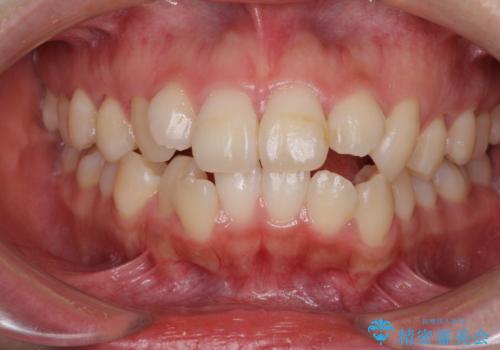

- 口元の突出感を気にして来院された患者様です。

診断の結果、上顎左右第一小臼歯4本抜歯により、叢生を解消するとともに口元を引っ込めていくことが望ましいと判断しました。